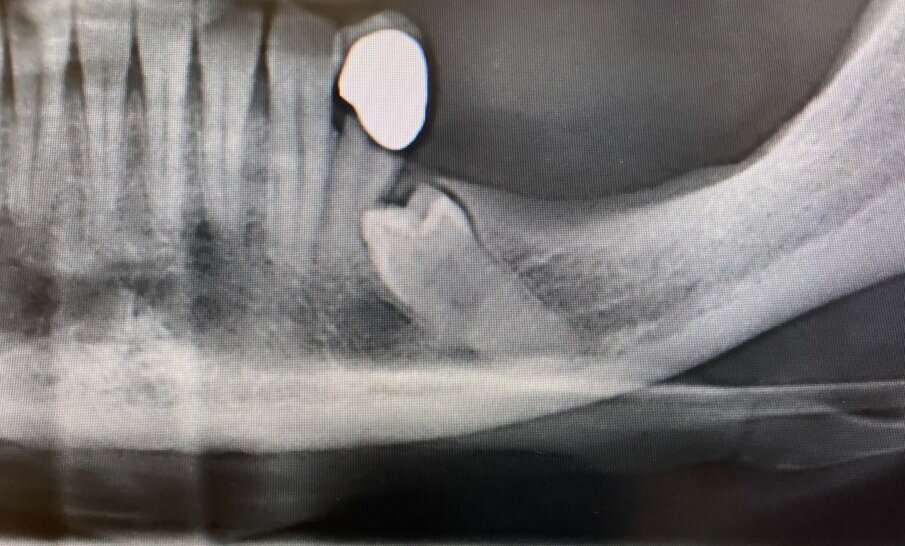

Il caso clinico presentato riguarda una paziente donna di anni 55 che presenta l’elemento 3.5 in inclusione totale in stretto rapporto con il canale alveolare come si evince dalle indagini radiologiche eseguite (opt e tac cone beam) (Figg. 1, 2).

Considerata la necessità di eseguire un riabilitazione implantoprotesica della sede edentula si è resa necessaria l’avulsione dell’elemento incluso con tecnica piezoelettrica che ci ha permesso di ridurre al minimo l’osteotomia e preservare l’integrità del nervo la cui emergenza si trovava esattamente in corrispondenza della corona del 3.5 (Figg. 3-9).

Fig. 2 - Sezione tac che evidenzia il rapporto di continuità con il nervo alveolare.